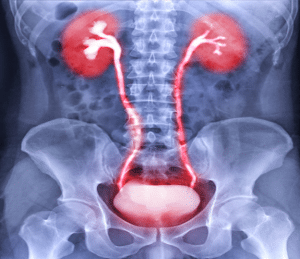

Intravenous Pyelogram (IVP): An older technique in this system where a contrast dye is administered intravenously, and fluoroscopic images are taken while the dye goes through the renal and urinary system. Contains details of the kidney and the urinary system and how they work and their formation.

Intravenous Pyelogram (IVP)

Fasting and bowel preparation may be required. Hydration is encouraged. The patient lies on an X-ray table. Iodinated contrast is injected intravenously. X-ray images are taken at various time intervals to capture the excretion of the contrast through the kidneys, ureters, and bladder.

X-ray Machine: These are utilized in imaging the urinary tract with an objective of observing lining of the opening of the ureter into the bladder.

Iodinated Contrast Media: Given intra-venously for the purpose of outlining the kidneys, the ureters and the bladder.

Compression Devices: Applied prior to the procedure to decrease the rate of urination and to improve the visibility of the urinary tract.